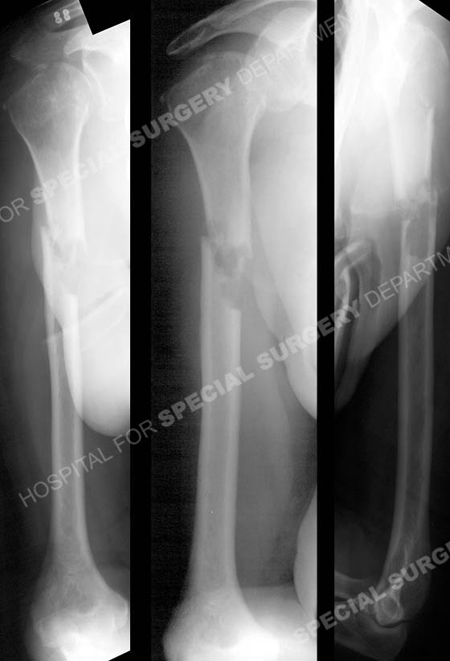

Anteroposterior and lateral radiographs reveal a right-sided pathologic mid-shaft humeral fracture and evidence of lytic lesions on the humeral head.

A 70-year-old male slipped and fell while skiing, landing on his outstretched right arm. Radiographs at the local hospital revealed a right-sided pathologic mid-shaft humeral fracture and evidence of lytic lesions on the humeral head. His right arm was placed in a fracture splint and he was referred to David L. Helfet, MD at the Orthopedic Trauma Service at Hospital for Special Surgery for definitive fracture management. Additional tests were performed to further evaluate the pathologic fracture and metastatic lytic lesions. Fracture reduction and fixation was planned and performed using an expandable retrograde intramedullary humeral nail. He followed up with an oncologist for further evaluation and treatment. He returned for regular follow-up and his pathologic humeral fracture healed uneventfully. At his latest follow-up appointment at 6 months he presents with excellent radiographic and clinical results including a healed pathologic humerus fracture in excellent alignment with maintenance of reduction and fixation and he returned to his activities of daily living with resolution of pain.